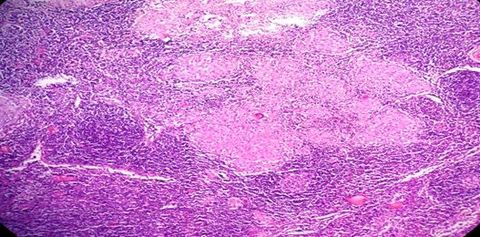

TISSUE TYPE: lymphocyets every where... where am I ??? xD PATHOLOGY: inflamatory granuloma with caseation in the center .. eosinophilic Langhan's cells (an orphan cell in the center) ^^ DIAGNOSIS: tuberculous lymphadenitis KEY: LYMPHOCYTES + CASEATION